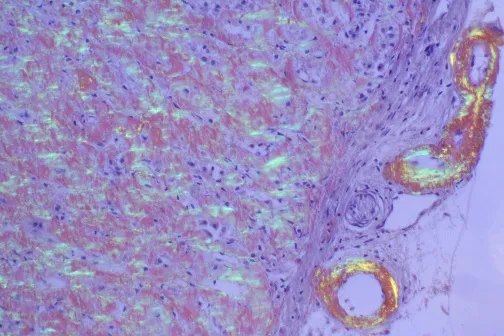

⭐ Histological Hallmark: Diagnosis requires tissue biopsy showing Congo Red staining, which produces a pathognomonic apple-green birefringence under polarized light.

⭐ Congo Red Staining: Regardless of the protein type, all amyloid deposits show characteristic apple-green birefringence under polarized light after staining with Congo red. This is a pathognomonic finding.

⭐ The pathognomonic finding is apple-green birefringence of Congo Red-stained tissue when viewed under polarized light. Without this, it's not amyloidosis.

- The pathognomonic finding is Congo red staining that reveals apple-green birefringence under polarized light.